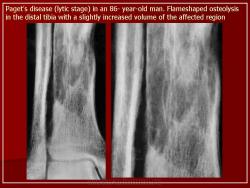

I стадия (литическя) — острая стадия, определяется деструкция кортикального слоя в виде очагов пламени или в форме клина.

В монооссальных случаях, частота которых, согласно публикациям, начинается от 10-20% доходя до почти 50%, дифференциальный диагноз может быть гораздо сложнее. В огромном большинстве случаев БП, наличие неоднородных участков костного склероза или остеолиза с искажением трабекулярной архитектуры в сочетании с кортикальным утолщением и фокальным утолщением кости практически патогномоничен для данного заболевания. Бедренная кость является второй наиболее распространенной монооссальной локализацией после таза. В случаях, когда имеется ее дистальное поражение, рентгенологические признаки, характерные для БП, выявляются с меньшей частотой или менее выражены, так что дифференциация с другими процессами, в частности, опухолевыми, может быть затруднена.